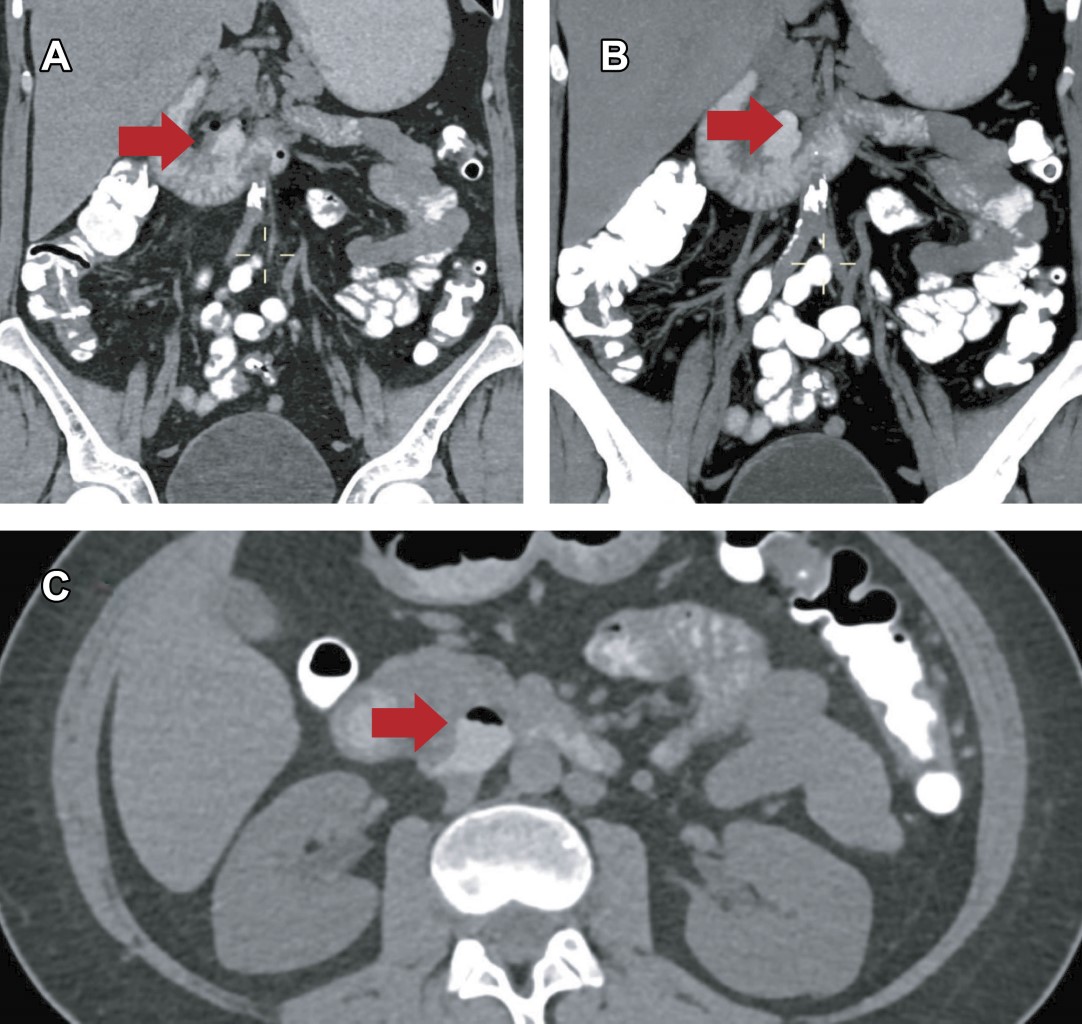

Tras seis días de vigilancia manteniendo presión arterial media (TAM) entre 65-70 mmHg, FC 60-75 lpm, FR 14-16 rpm, saturación de oxígeno > 94%, temperatura 36-36.8 °C, con NP y clínicamente asintomática, se realizó control tomográfico, en donde se observó divertículo con menor cantidad de aire extraluminal (Figura 2), mejoría en laboratorios (Tabla 1) y ausencia de síntomas, por lo que se inició dieta líquida a tolerancia, con progresión a dieta específica, con disminución progresiva de NP. Se avanzó a dieta blanda, sin grasas ni irritantes; una vez completados siete días de tratamiento antibiótico, se suspendió ertapenem y fluconazol. A los diez días, la paciente presentó mejoría en sintomatología abdominal, adecuada evolución clínica y tolerancia al 100% de sus requerimientos nutricionales, por lo que fue dada de alta.

Actualmente, a cuatro meses del evento inicial, la paciente se ha mantenido estable; sus laboratorios están en la normalidad (Figura 1) y los principales síntomas que presenta son secundarios a enfermedad por reflujo gastroesofágico, razón por la que se encuentra en tratamiento con inhibidores de la bomba de protones (IBP), procinético y protector de mucosa.